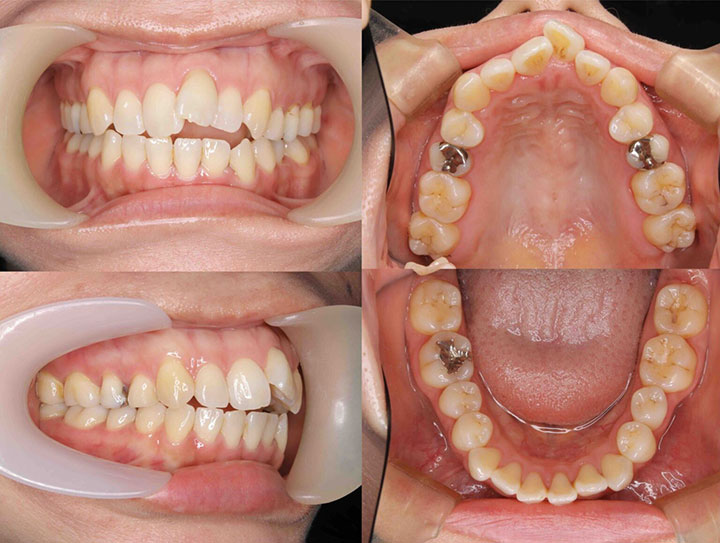

口の閉じ辛さの治療

治療期間:1年5ヶ月

上下顎4番を抜歯して、前歯を後方に移動しました。